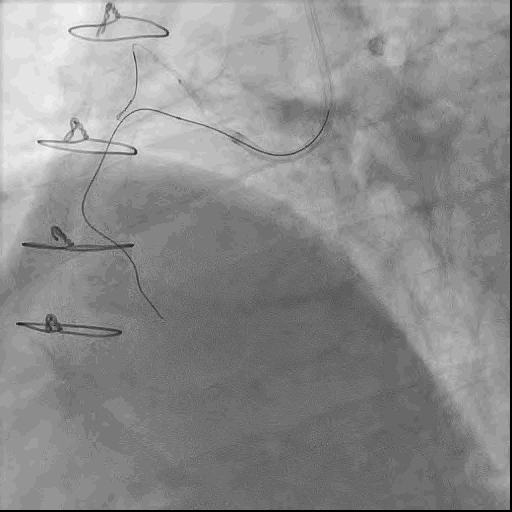

手术策略:正向开通RCA-CTO病变。

首先置入Cosair135微导管,使用XTR导丝反复尝试无法通过闭塞段,更换UB3导丝后成功通过闭塞段。

冠脉造影提示RCA闭塞钙化负荷较重,使用球囊锚定技术,小球囊反复扩张闭塞病变。

后更换微导管送入RCA中远段,并更换工作导丝至左室后支远端。